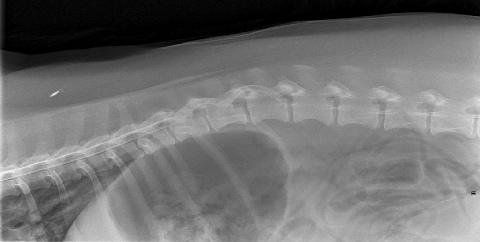

I metodi diagnostici utilizzati dai neurologi veterinari comprendono

esame fisico e racolta dell'anamnesi,

valutazione radiografica (in bianco nero e con mezzo di contrasto-MIELOGRAFIA)

analisi del liquido cerebrospinale,

risonanza magnetica e TC,

test elettrodiagnostico che comprende la valutazione della velocità della conduzione nervosa.

esame di potenziali evocati uditivi-BAER.